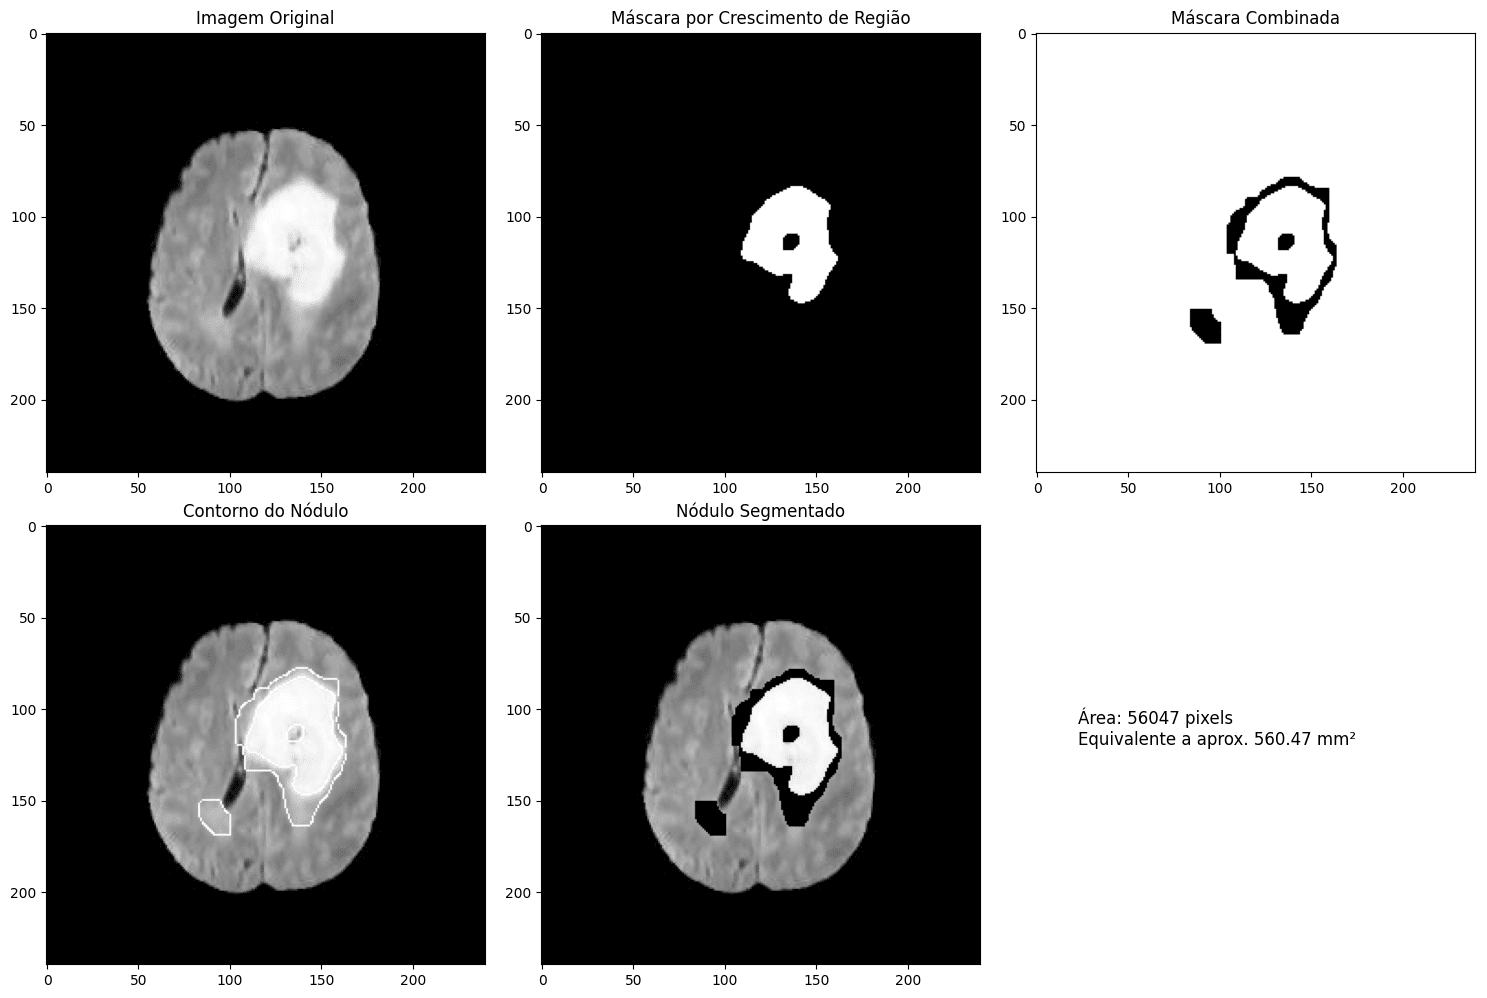

A segmentação de nódulos em imagens médicas é um dos desafios mais importantes para diagnósticos mais rápidos e precisos. Para resolver esse problema, o professor Pesquiador desenvolveu uma abordagem inovadora que combina física teórica e inteligência artificial. Seu método utiliza o modelo de difusão anisotrópica de Perona-Malik para suavizar imagens médicas, preservando bordas essenciais sem comprometer detalhes. Além disso, um algoritmo de crescimento de região realiza a segmentação inicial, garantindo uma delimitação precisa das áreas de interesse.

Para refinar os resultados, a metodologia incorpora a Matriz de Coocorrência de Níveis de Cinza (GLCM), permitindo a extração de características texturais que diferenciam tecidos normais de áreas suspeitas. Como resultado, a técnica demonstrou alta eficiência na segmentação de nódulos em testes realizados com imagens de tumores cerebrais. Além disso, a abordagem oferece métricas quantitativas para a caracterização dos nódulos, o que pode facilitar a detecção precoce e melhorar a análise de lesões médicas.